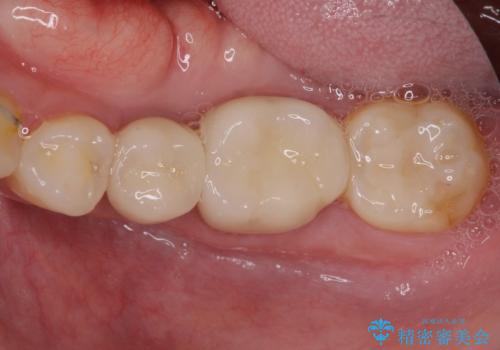

- 右下の欠損部の治療を希望して来院された患者様です。

部分矯正を行った後にインプラント埋入と手前の歯の根管治療を行い、その後補綴治療を行うこととしました。

治療途中より、上の歯や反対側の銀歯、上顎前歯の色合いや下顎前歯のデコボコが気になってきたため、全てを治療することとしました。